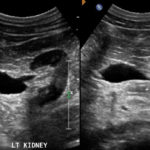

1-Hypertrophied column of Bertin

أعتقد بأن هذا من أهم المتغيرات التي قد يشتبه في كونها ورم. هي ببساطة تضخم لنسيج الكلية parenchyma إلى الداخل sinuses مرورا بين الأهرامات الكلوية medullary pyramids.

يميزه تناسق echogenicity بينه وبين باقي parenchyma بالإضافة لعدم وجود ارتفاع أو تغير ملحوظ في قراءات colour Doppler. غالبا لا يزيد عرضه عن ٣ سم.